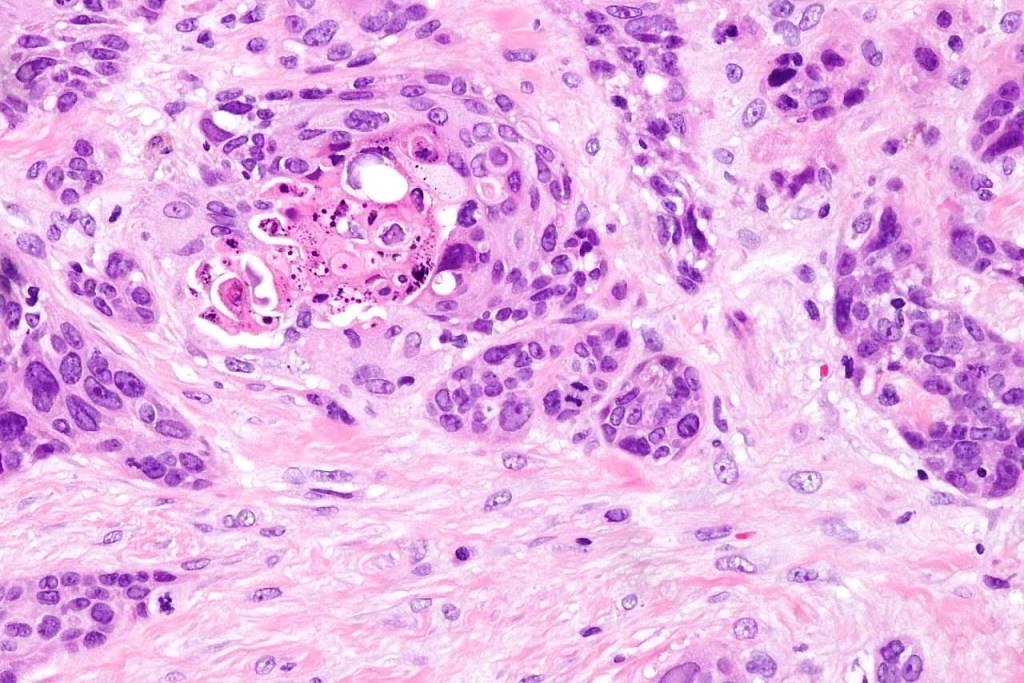

•Variable pleomorphism and mitotic activity

•Deep part may show both ducts and glands